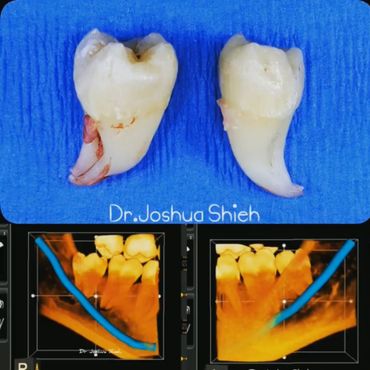

A surgical extraction is a more complex procedure. It is used if a tooth may have broken off at the gum line or has not come into the mouth yet. Surgical extractions are commonly performed by general dentists or oral surgeons depending on the case. Sometimes it’s necessary to remove some of the bone around the tooth or to cut the tooth in half in order to extract it. For surgical extractions, patients receive local anesthetic. A suture is usually required to control bleeding and facilitate healing.